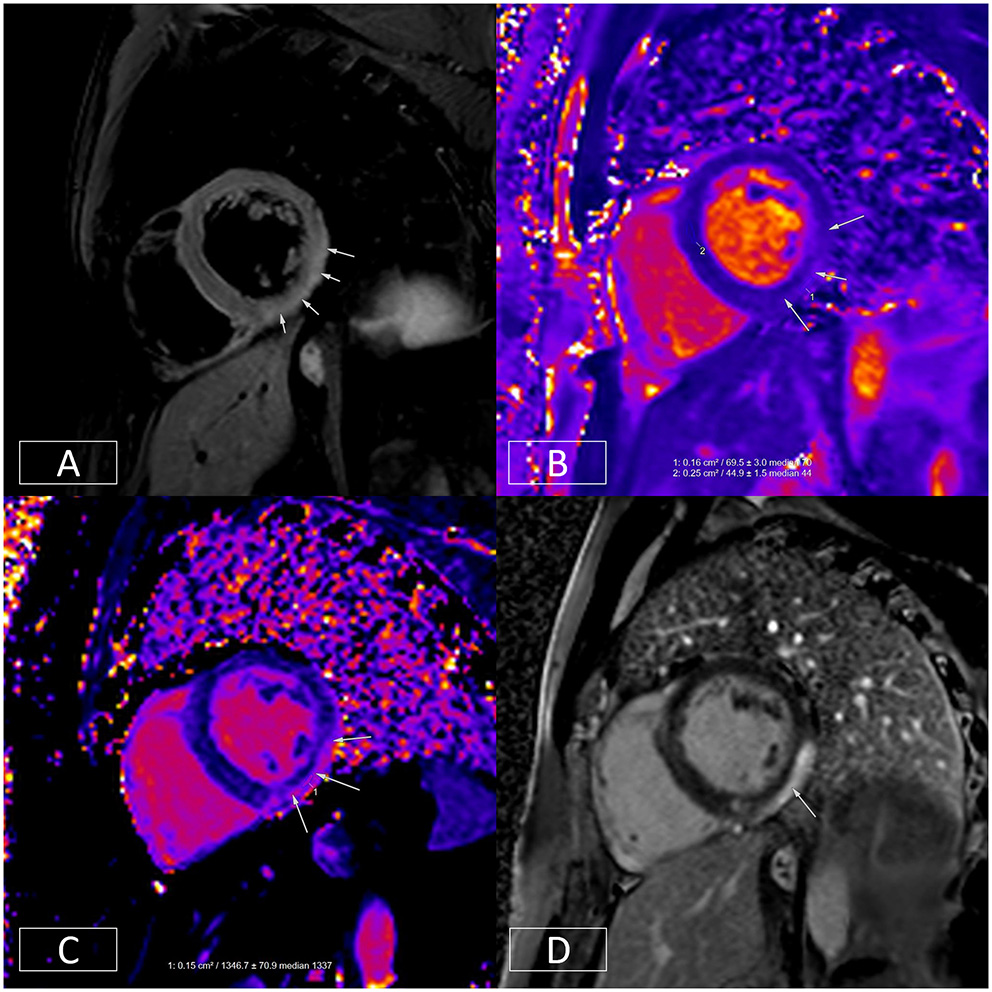

Figure 5

Multiparametric evaluation of a patient with acute myocarditis. (A) Depicts increased T2 signal in the mid-inferior and lateral walls in an epicardial to mid-wall distribution. The absolute T2 time in the inflamed area is increased to ~70 ms (B) whereas the remote myocardium in the septum has a normal T2 time of 45 ms (normal < 55 ms). (C) depicts increased native T1, another marker of tissue injury. This is raised at 1,347 ms in the epicardium of the mid-inferior and lateral walls (normal range: 890–1,035 ms on this platform at 1.5T). (D) illustrates epicardial to mid-wall enhancement of the mid-inferior and lateral walls, which spares the sub-endocardium (typical of myocarditis).